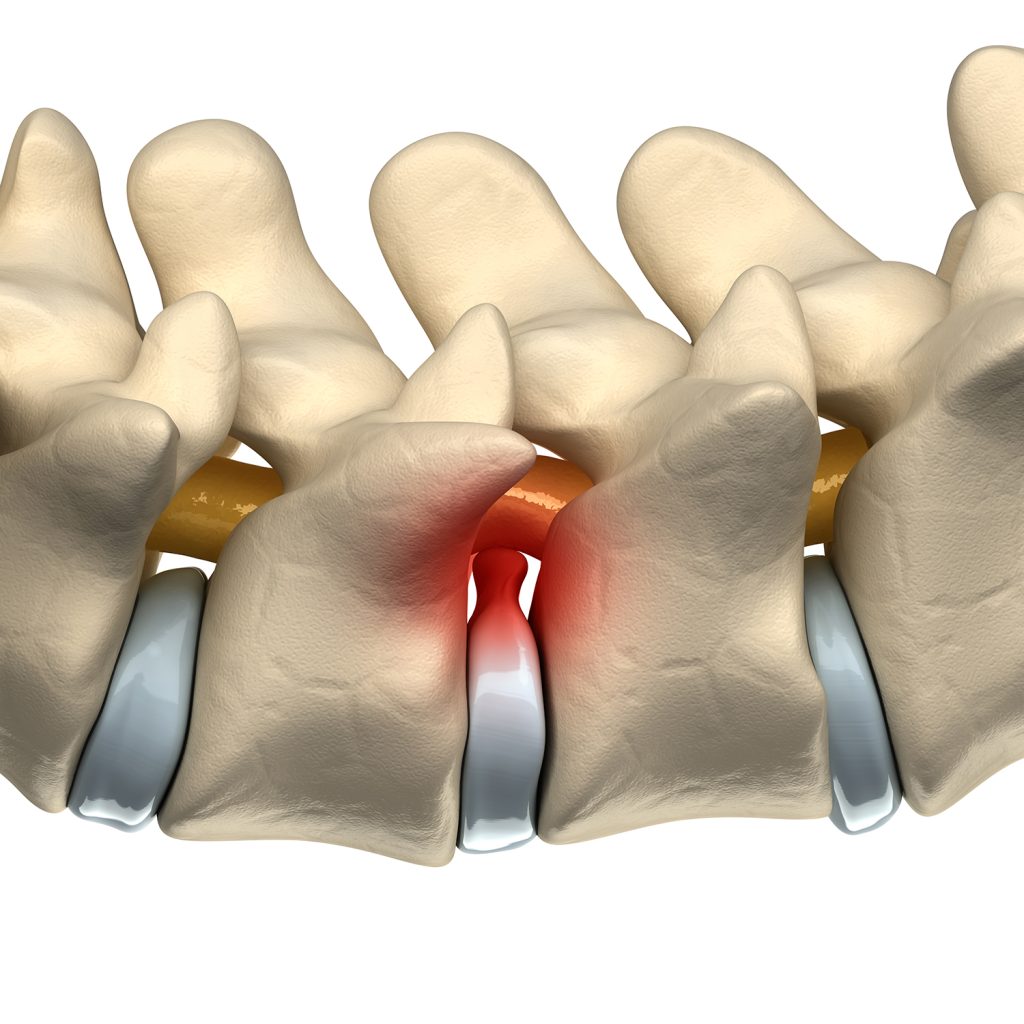

Zenuwbanen lopen van de kop naar de staart door het ruggenmerg. Het ruggenmerg is erg kwetsbaar. Rondom het ruggenmerg zitten de wervels die het ruggenmerg beschermen. Tussen deze wervels zitten tussenwervelschijven. Die fungeren als schokabsorbeerder en stootkussen bij het bewegen van de wervelkolom. De tussenwervelschijf bestaat uit twee delen: een buitenste peesachtige ring (annulus fibrosus) en een gelatine-achtige kern (nucleus pulposus). Een (rug)hernia (Hernia Nuclei Pulposi) ontstaat als er materiaal van de tussenwervelschijf tegen het ruggenmerg aan duwt en daardoor pijn, slapte van de spieren of zelfs verlamming veroorzaakt.

- Type I ontstaat door scheuring van de buitenste pezige ring van de tussenwervelschijf, waardoor kernmateriaal in het ruggenmergkanaal wordt gestuwd.

- Type II ontstaat doordat het kernmateriaal tegen een verzwakt deel van de buitenste ring van de tussenwervelschijf duwt, waardoor deze uitpuilende ring op het ruggenmerg of uittredende zenuwen drukt.